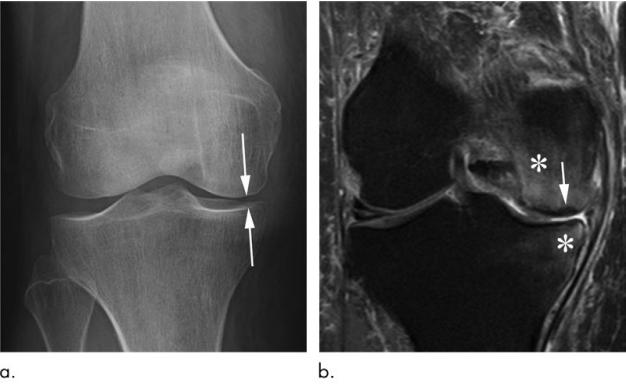

先和大家分享一个病例:这是一位69岁女性的膝关节软骨下不全性骨折,其表现为膝关节疼痛急剧恶化,无外伤病史。

图片a右膝正位片显示关节间隙内侧室变窄(箭头所示),无骨赘。没有骨坏死或软骨下不全骨折的迹象。

图片b与a同时应用冠状中等重量脂肪抑制MRI显示股骨内侧髁软骨下不全骨折,关节面无塌陷(箭头)。此外,还有明显的股骨和胫骨骨髓水肿(*)。